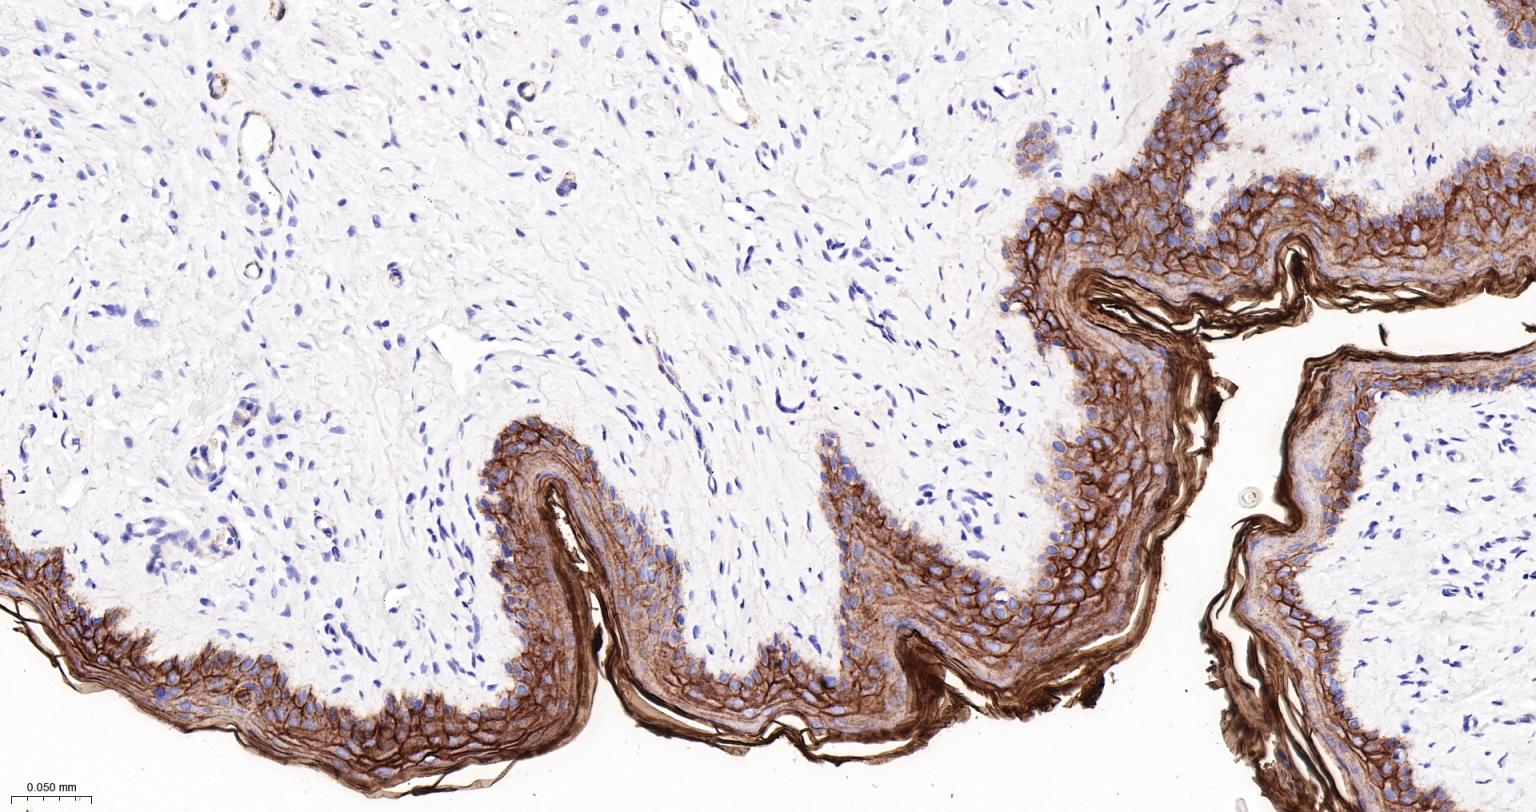

Paraformaldehyde-fixed, paraffin embedded Rat Skin; Antigen retrieval by boiling in sodium citrate buffer (pH6.0) for 15 min; The section was incubated with PERP Monoclonal Antibody, Unconjugated (bsm-61725R) at 1:200 overnight at 4°C, followed by conjugation to the bs-0295G-HRP and DAB (C-0010) staining.